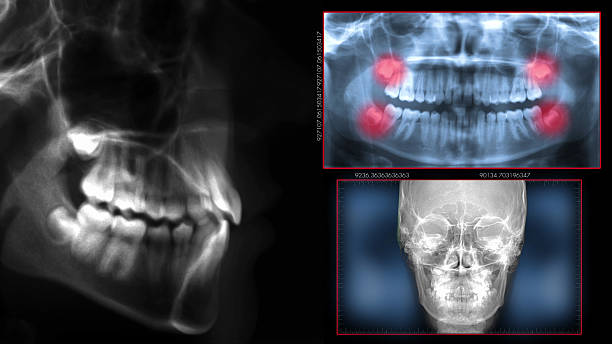

Advanced Technology

We use digital X-rays and 3D imaging to accurately assess wisdom teeth for safe, efficient removal. -

- Initial Consultation : The process begins with a thorough consultation, digital X-rays, and a detailed discussion of your treatment plan.

Why Are Wisdom Teeth Removed?

- Pain and Discomfort : Impacted wisdom teeth can cause severe pain and swelling

- Infections : Partial eruption can lead to bacterial infections, resulting in gum disease or abscesses.

- Crowding and Misalignment :Wisdom teeth can push other teeth out of alignment.

- Cyst Formation :In some cases, impacted teeth may develop cysts, damaging surrounding bone and teeth.